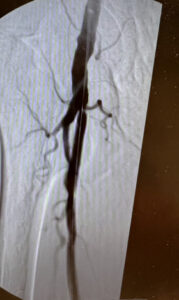

Ενδαγγειακή επαναγγείωση της επιπολής μηριαίας αρτηρίας

Ενδαγγειακή αποκατάσταση απόφραξης της επιπολής μηριαίας αρτηρίας